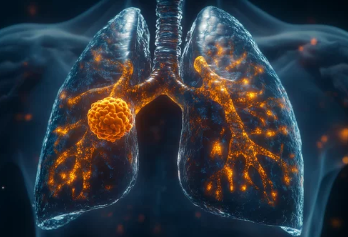

폐기흉(기흉, Pneumothorax)은 폐에 공기 주머니(기낭)가 터지거나 손상되면서 공기가 흉강(가슴막)으로 새어나와 폐가 수축하는 질환이다.

2. 폐기흉이 발생하는 주요 원인

① 원발성(자발성) 폐기흉 – 젊고 마른 체형에서 흔함

✔ 특별한 원인 없이 갑자기 발생(선천적으로 폐 기포가 약한 경우)

✔ 흡연, 마른 체형(장신 & 저체중), 유전적 요인 등이 위험 요소

② 이차성 폐기흉 – 기존 폐 질환이 있는 경우

✔ 만성 폐질환(만성 폐쇄성 폐질환, 폐기종, 결핵, 폐렴 등)으로 인해 발생

✔ 기저 질환이 있는 경우 증상이 더 심할 수 있음